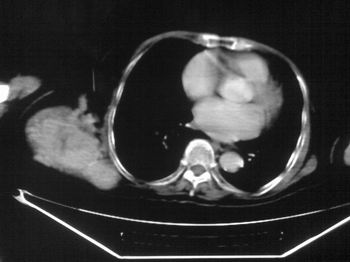

以下是引用dyqct在2007-9-11 16:52:00的发言:[br]支持右肩胛骨恶性肿瘤,性质不好定。

以下是引用zhangxu5888在2007-9-11 16:25:00的发言:[br]有侧肩胛骨溶骨性破坏且见软组织成分,增强软组织强化明显,中央见低密度坏死区!根据病史10年,考虑良性肿瘤恶性变!性质待定!

以下是引用老爱克斯新网客在2007-9-11 18:22:00的发言:[br]应该是良性肿瘤恶变,但因晚期破坏严重不能见到原来肿瘤征象无法判断,